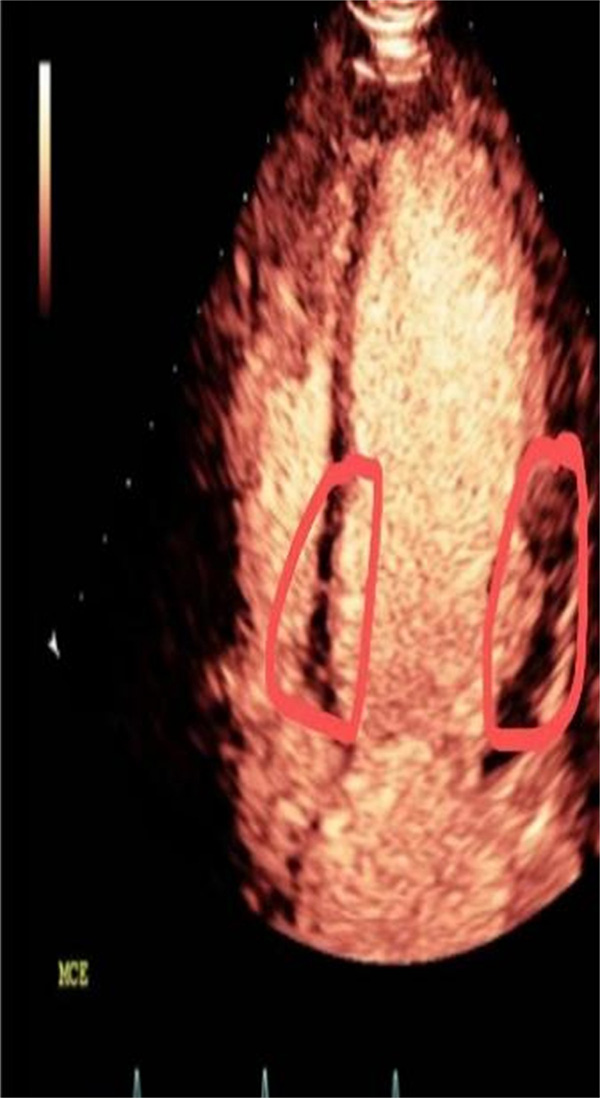

2022年也是超声心动全面发展的一年,2022年1月至今,心内科开展了心脏超声造影,包括左心腔超声造影、左心肌超声造影和右心超声造影,顺利完成了左心室血栓评估、心尖肥厚性心肌病、心肌致密化不全、PCI手术患者术前、术后心肌灌注评估、透析患者心肌的评估。

左心室血栓 心尖肥厚性心肌病,“黑桃”改变PC术后心肌灌注

心脏超声造影通过外周静脉注射超声造影剂(ultrasound contrast agent,UCA),实时动态且更清晰地观察心肌灌注及心腔,反映心脏结构、功能及其冠脉微循环。

定量评价左室容量、射血分数、节段性运动异常(与核素显象、磁共振有良好的相关性),观测心脏内部细微解剖结构(左室心尖肥厚、心肌致密化不全、心尖血栓、心尖室壁瘤),能更清晰的显示左心房的解剖特征,尤其是左心耳,对鉴别血栓、伪像、明显自发显影和左心耳正常解剖结构有很大帮助。